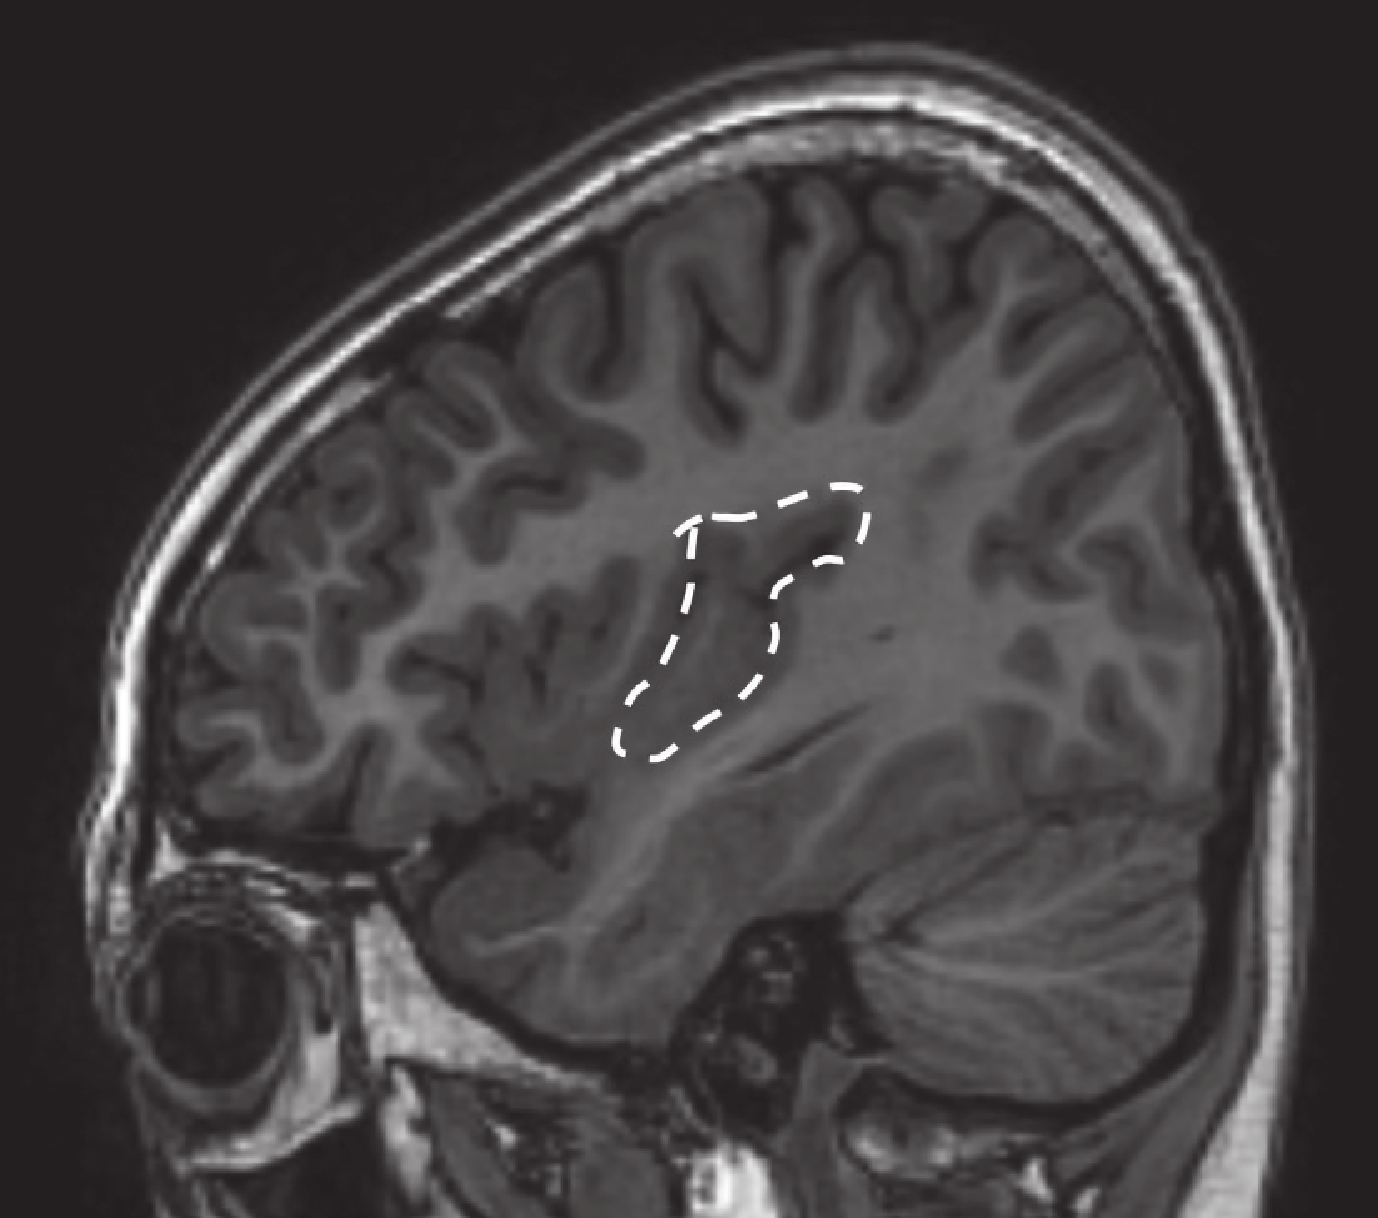

患者于 2016 年 8 月 3 日行致癇區切除術,切除范圍包括右側全島葉切除(包含前環島溝前壁),右側顳極、杏仁核,顳橫回及顳蓋。術后未出現神經功能缺失,無并發癥。術后病理為局灶性皮層發育不良(FCD Ib)。術后 MRI 見圖 16。